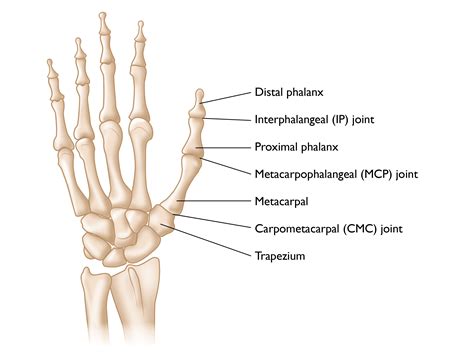

Understanding the Proximal Phalanx

The proximal phalanx is the first bone in the fingers, located between the metacarpal bones of the hand and the middle phalanx. It plays a critical role in the movement and stability of the fingers. A fracture in this bone can significantly impact hand function and mobility.